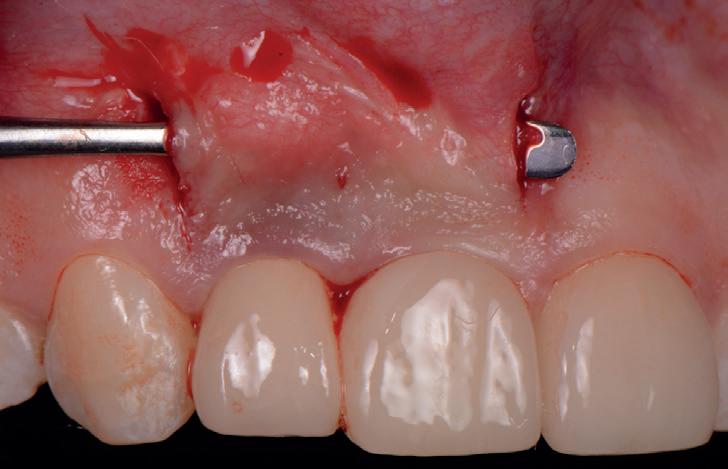

SITE AUGMENTATION Reconstituirea țesutului moale periimplantar și papilar în zona estetică

RECONSTITUIREA țesuturilor moi periimplantare. Scopul acestui raport de caz este de a demonstra procedurile chirurgicale utilizate pentru corectarea unui defect al țesuturilor moi periimplantare folosind țesutul moale interdentar în combinație cu tuberozitatea ca locație donatoare de țesut conjunctiv, utilizând o abordare prin tunelizare într-o zonă estetică.